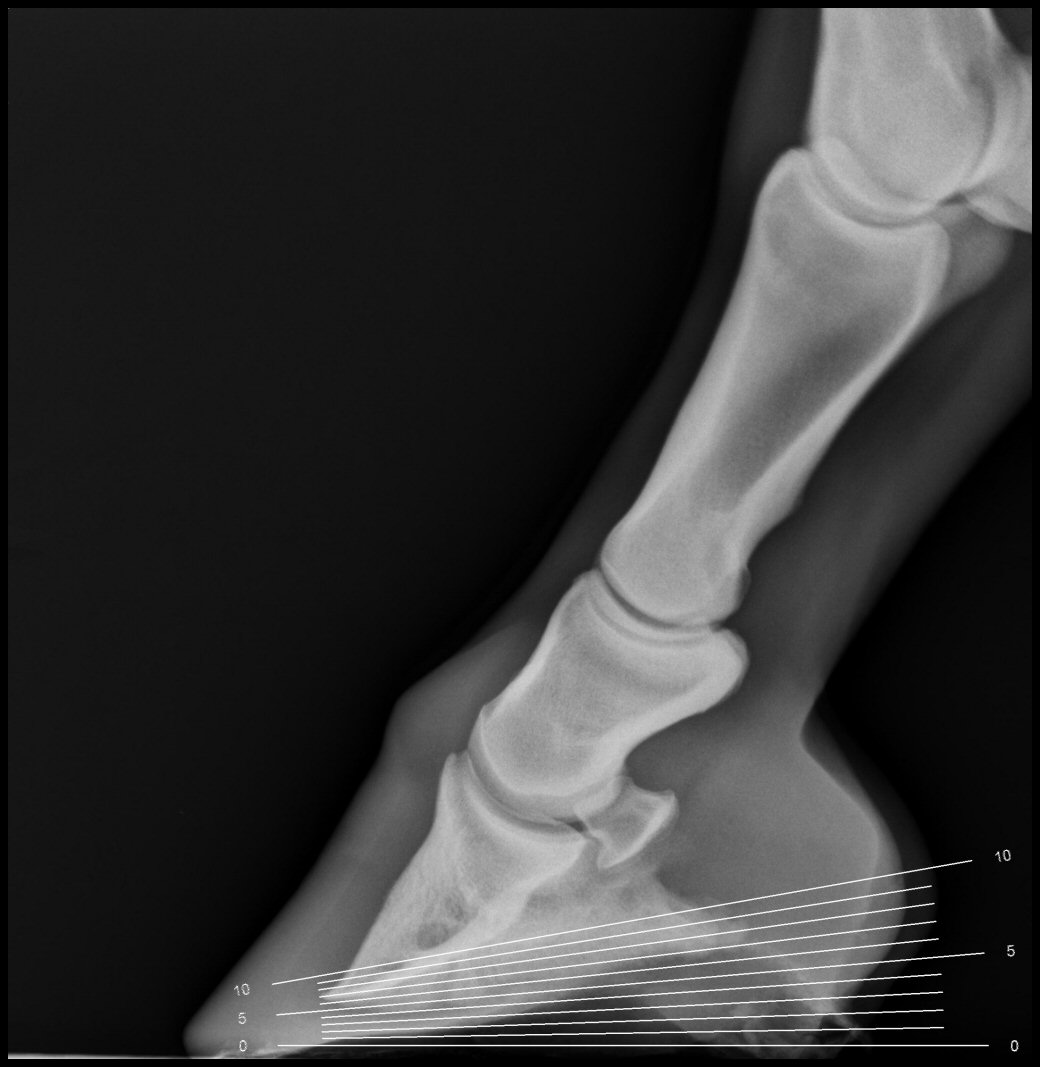

Measuring the Equine Hoof in Radiographs — a Focus on Calibration by

Measuring the Equine Hoof in Radiographs — a Focus on Calibration by Horse Hoof Angle The angle of the hoof should match the angle of the dorsal surface of the pastern. The hoof is a complex structure, comprised of specialized layers and components that together support the horse’s body weight, absorb shock, and provide traction for movement. Some argued that the best angle was 45 degrees, while others held up 56 degrees as the ideal.. Horse Hoof Angle.